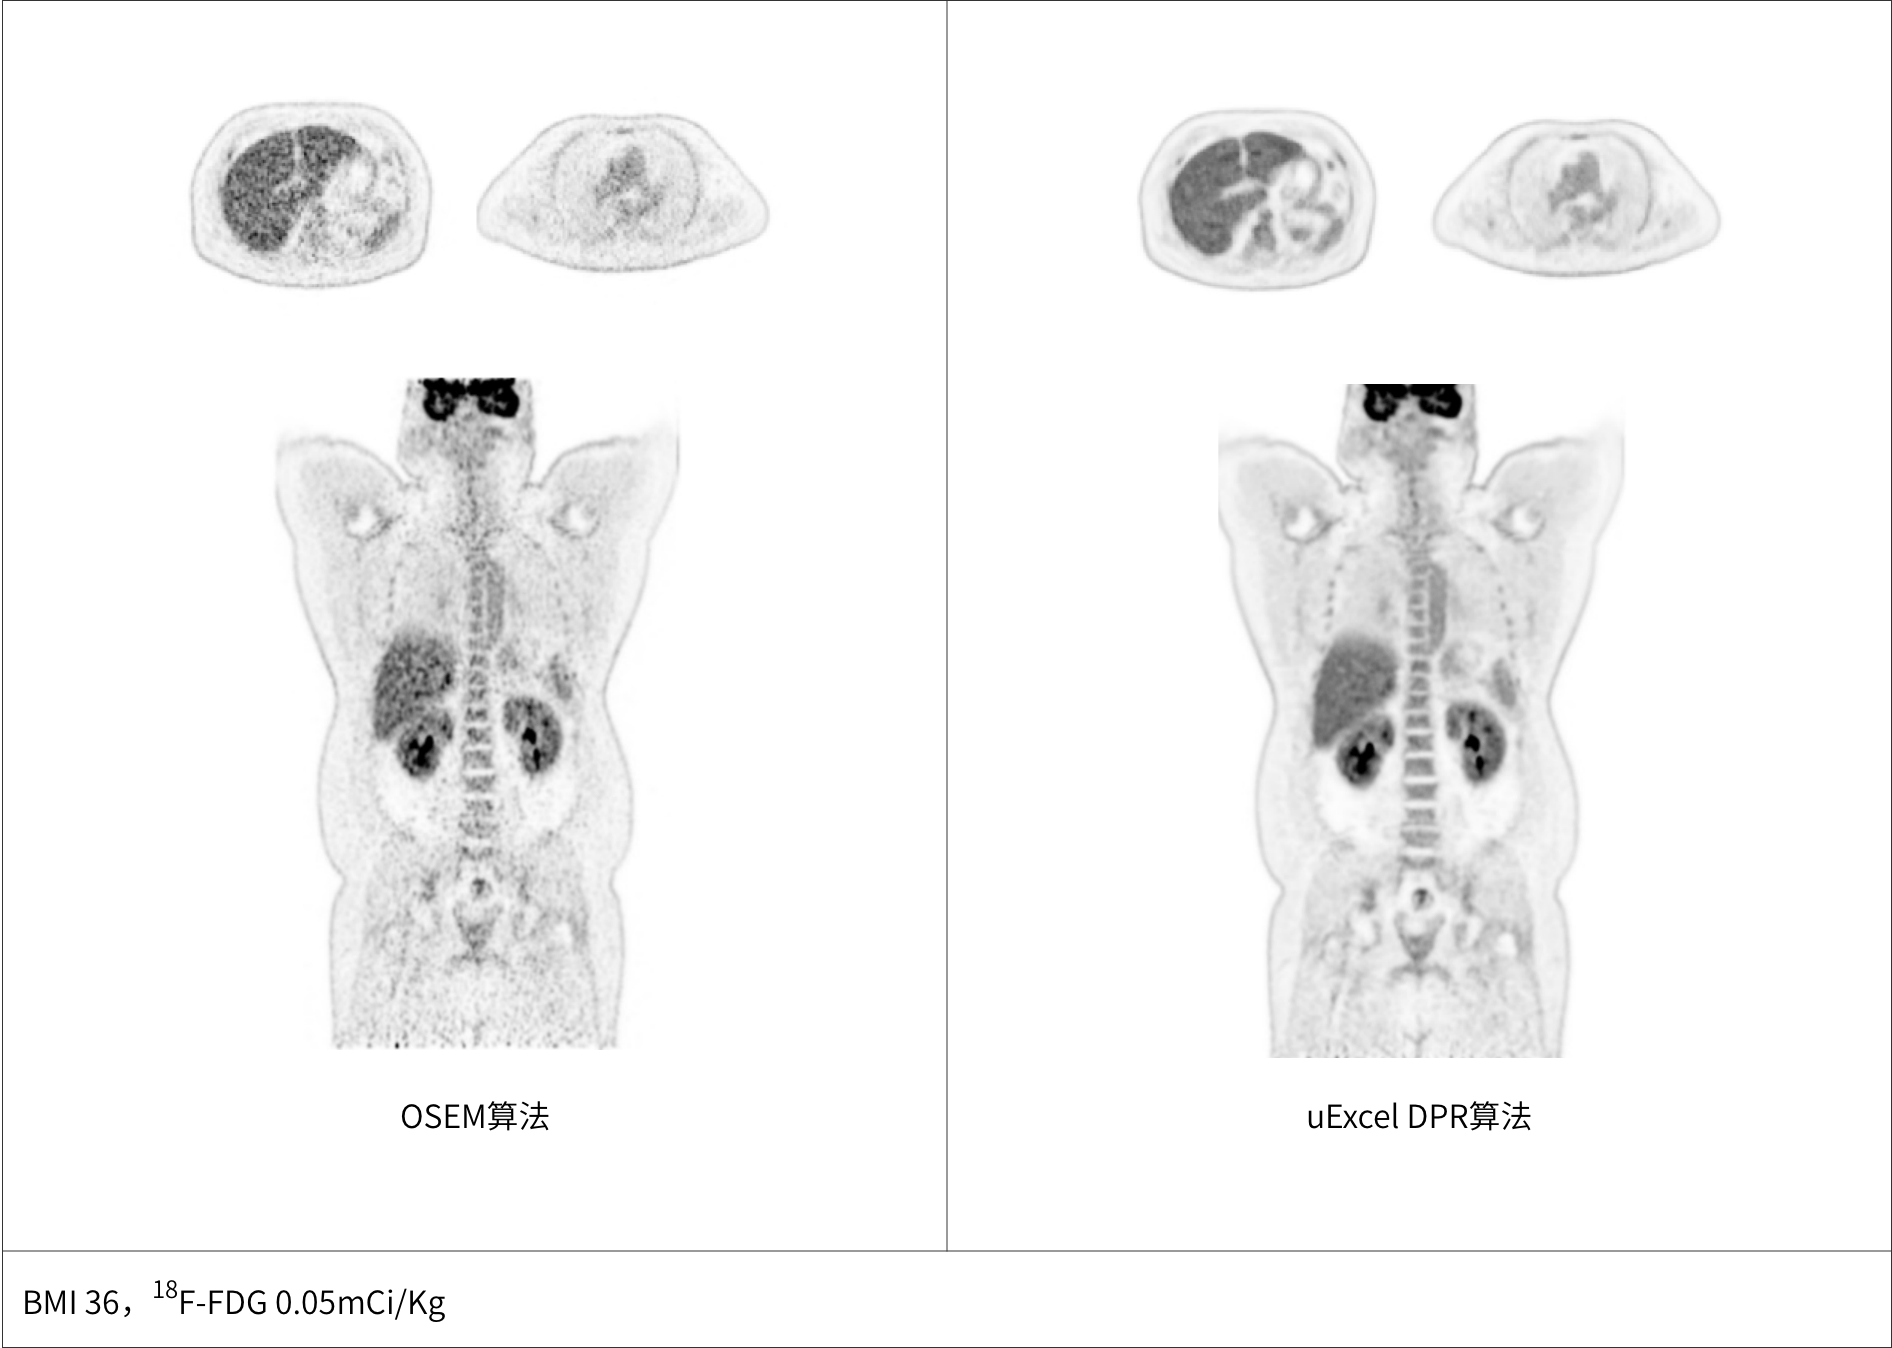

uExcel DPR*全面优化PET-CT扫描条件

兼顾噪声、对比度、分辨率等多维度进行分布渐进式学习优化

极低噪声、高对比度uEXPLORER海量优质图像训练集有效保证输出结果的可靠性

同时实现图像对比度、噪声、信噪比三重优化

大体重患者主动脉血管结构清晰显示